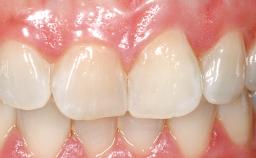

Late Placement of an Implant in a Maxillary Left Central Incisor Site

A 36-year-old female patient was referred for the replacement of the upper left central incisor (tooth 21), which had fractured. Although the tooth had been asymptomatic for many years, the crown began to loosen, at which time she presented to her dentist for an assessment. Teeth 21 and 22 had both been endodontically treated many years previously. She was a healthy individual and a non-smoker.

On examination, the patient had a low lip line and only displayed the coronal half of the anterior teeth when smiling.

Prosthesis Type FDP